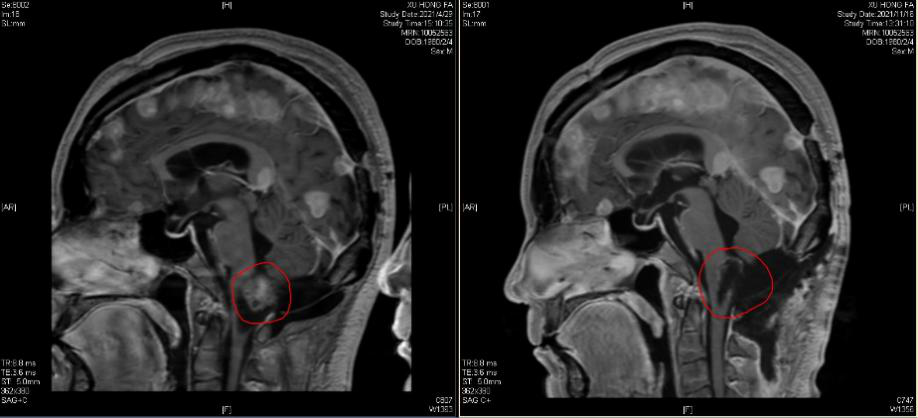

10年前,徐先生第一次找到王贵怀时,已经是多个椎管内神经纤维瘤、多发颅内脑膜瘤、双侧听神经鞘瘤的复杂状态,王贵怀先后主刀6次,为其切除了颅脑、脊髓内的肿瘤,以优先保障住患者生存与肢体功能,但剩余的肿瘤仍在生长,这注定是一场拉锯战。2020年,徐先生到北京清华长庚医院复查时,王贵怀发现患者颅内脑膜瘤体积明显增大并已压迫脑组织,同时,脑干肿瘤体积也在增大。但同时切除颅内多个肿瘤的手术难度与风险较大,出于安全考虑,患者和家属选择先切除大脑深部的脑膜瘤的方案,对脑干肿瘤则随访观察。

今年11月,脑干肿瘤已经导致徐先生出现呼吸困难,下肢力弱,呕吐,心慌等症状,甚至一度呼吸停止,被紧急送到当地医院进行临时救治后,生命体征暂时稳定下来,但当地医院不具备脑干病变手术的条件,焦急之下,家属赶忙联系北京清华长庚医院神经中心。得知患者情况危急,王贵怀立刻通知家属在符合当地疫情防控要求的前提下,迅速将患者转至我院,评估手术可能。又值北京疫情严控时期,神经中心在严格遵守疫情防控政策,完善相关筛查后,医疗团队快速开展术前评估。

这是王贵怀第七次为患者行肿瘤切除手术,也是最难的一次——肿瘤根部就在脑干的背侧,此前的呼吸停止也已预示着肿瘤对脑干中枢造成的致命压迫。11月11日,在患者和家属的高度信任下,王贵怀与麻醉科通力配合,挑战生命禁区,由于肿瘤与脑干关系过于紧密,术中一度出现心率下降和血压不稳的危急表现,麻醉医师不得不要求暂停手术,等心率血压纠正以后再接续手术,如此反复几次,肿瘤才得以切除。